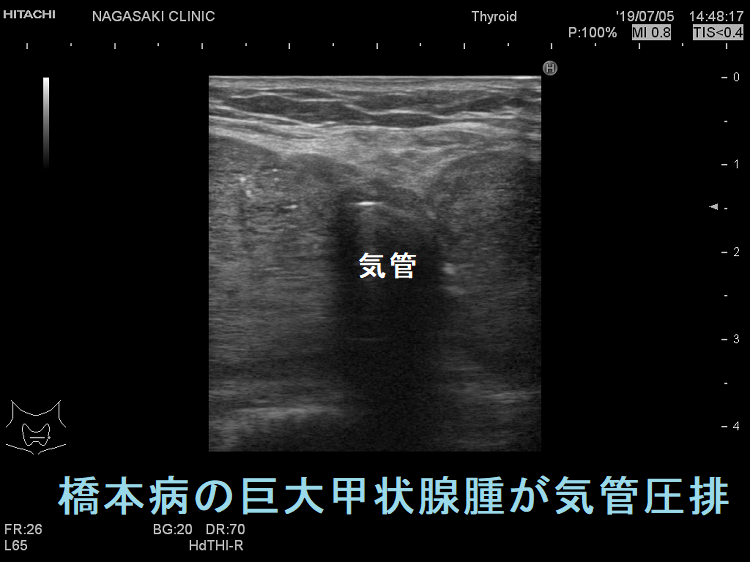

ケース① 橋本病巨大甲状腺腫(気管圧排)

ケース③ 橋本病の巨大甲状腺腫が気管圧排